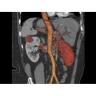

КТ аппарат GE Optima CT520 используется для диагностики широкого спектра заболеваний:

Кардиология

• Неинвазивная оценка состояния коронарных артерий.

• Диагностика атеросклероза и других сердечно-сосудистых патологий.